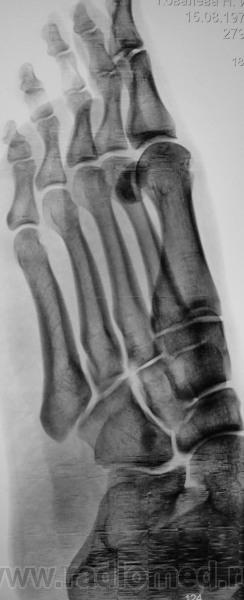

Пол пациента: Женский пол Тип патологии: Травма Область исследования: Скелетно-мышечная система Методы исследования: Rg Пациент направлен по поводу травмы. Случайная находка... https://radiomed.ru/sites/default/files/styles/case_slider_image/public/user/12/2.201310200016.jpg?itok=VzEdq3KK https://radiomed.ru/sites/default/files/styles/case_slider_image/public/user/12/3.201201010012_2.jpg?itok=US4gX77V https://radiomed.ru/sites/default/files/styles/case_slider_image/public/user/12/4.201310200014.jpg?itok=l6zzwcyf ID:32564 Пнд, 21/10/2013 - 23:57 #1 И.Бондаренко Не на сайте Был на сайте: 4 дня 2 часа назад Зарегистрирован: 13.09.2011 - 22:55 Публикации: 9206 И что это? Такое встречается, описываю как участок склероза или внимания не обращаю. Втр, 22/10/2013 - 16:54 #2 Pilulia Не на сайте Был на сайте: 7 лет 9 месяцев назад Зарегистрирован: 02.09.2011 - 14:27 Публикации: 14 или добавочная сесамовидная кость, как вариант.. Втр, 22/10/2013 - 22:16 #3 Катенёв Валенти... Не на сайте Был на сайте: 7 лет 2 недели назад Зарегистрирован: 22.03.2008 - 22:15 Публикации: 54876 Pilulia wrote: или добавочная сесамовидная кость, как вариант.. Добавочная? Сесамовидная?

И что это? Такое встречается, описываю как участок склероза или внимания не обращаю.

или добавочная сесамовидная кость, как вариант..

Добавочная?

Сесамовидная?